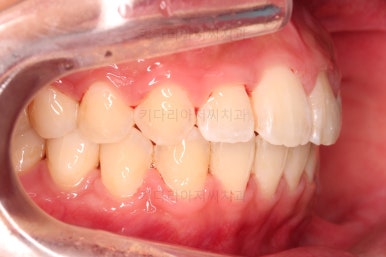

5. 마무리와 치료 종료

마무리가 잘 되었습니다.

큰 문제는 없었지만, 약간 삐뚤었던 치열이 가지런하게 정렬이 잘 되었고요.

맞물림도 매우 좋고, 뻗친 앞니 각도도 매우 좋아졌습니다.

입 안의 모습만 보면 최상급의 마무리가 되었고요.

6. 전후 사진 비교

입매가 매우 좋아졌습니다.

과연 11개월의 치료결과가 맞나 싶을 정도로 깜짝 놀랄만큼 만족스러운 치료결과였는데요.